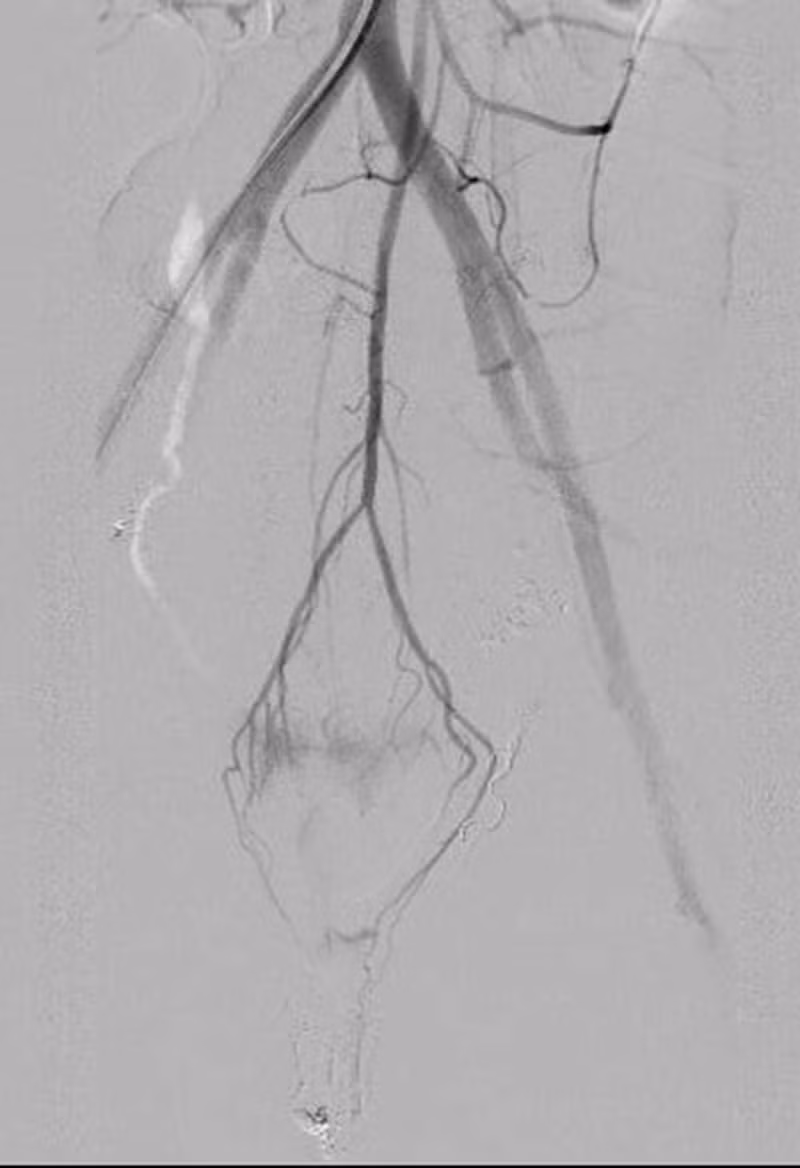

| Hình ảnh thoát thuốc vị trí động mạch tử cung trái và quanh trực tràng |

Tại Bạch Mai, các bác sĩ của Trung tâm Cấp cứu A9 và Trung tâm Điện Quang lập tức hội chẩn cấp cứu để đưa ra phương án chẩn đoán và điều trị cho người bệnh. Kết quả chụp MSCT cho thấy, bệnh nhân bị tổn thương chảy máu từ mạch máu quanh trực tràng.

“Bình thường, chúng tôi chỉ gây tắc nhánh mạch tổn thương và cầm máu tạm thời động mạch chậu trong hai bên. Tuy nhiên với bệnh nhân này, chúng tôi cần tìm thêm các nhánh chảy máu quanh trực tràng, gồm 6 nhánh mạch 2 bên: động mạch trực tràng trên, động mạch trực tràng giữa và động mạch trực tràng dưới”, BS CKII Phan Hoàng Giang cho biết thêm.